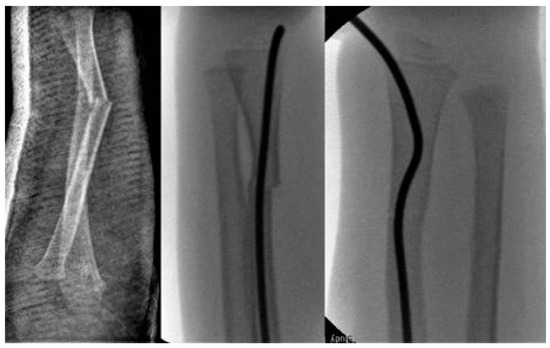

Scheme 4. Open forearm fracture leaving the fracture of the ulna to spontaneous correction.

The youngest patient was a two-year old boy, who presented with an unacceptable secondary displacement two weeks after trauma and, thus, this fracture became a rare indication for osteosynthesis in this age group (Scheme 2). The eldest was 17 years of age and did not show epiphyseal plates anymore (Scheme 3). This patient, however, suffered a new trauma 3 weeks later and underwent a redo-procedure in another hospital and, thus, was lost to follow-up. We even treated an open forearm fracture (on the ulnar side) with this technique (Scheme 4), leaving the fracture of the ulna to spontaneous healing and correction. This was because the risk of osteomyelitis due to intramedullary nailing of the open ulnar fracture to achieve a “nice X-ray” was estimated to be much higher than the risk of a remaining misalignment. Even a redo-procedure of a fracture that we had seen for the first time 4 weeks after an unacceptable K-wire osteosynthesis was successful, this time using a modification of the technique with a bend, rather than a kink distal to the fracture. Please note that the pre-bent nail pushed the 4-week-old fracture into a correct position without open reduction (Scheme 4). Last but not least, curiously, we saw one patient who suffered identical fractures in both arms, so we could perform the procedure twice in one operation (Scheme 5).